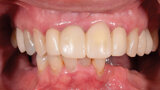

Rekonstrukce chrupu v dolní čelisti